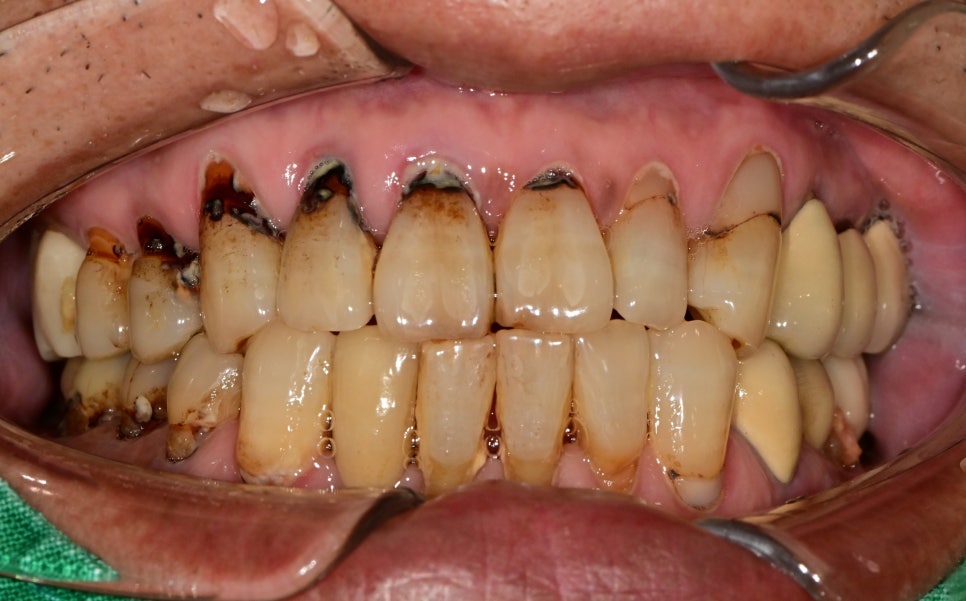

또 다른 환자분의 구강 내 모습입니다.

잇몸이 내려앉은 상태에서 효과적인 잇솔질이 안되는 상태에서

치석, 치태의 침착이 가속화되어 우식이 진행된 상태였습니다.